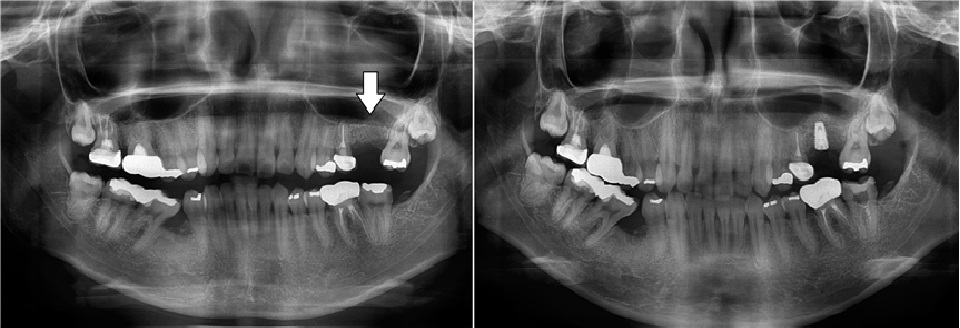

치료전후사진